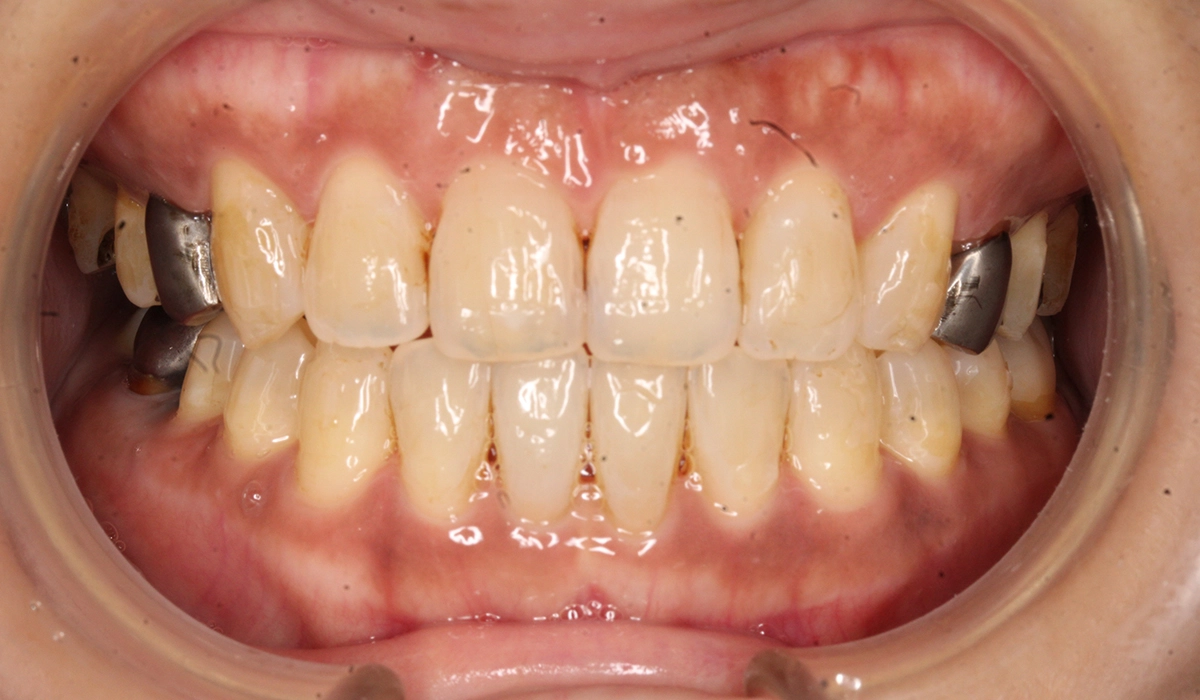

術前:正面